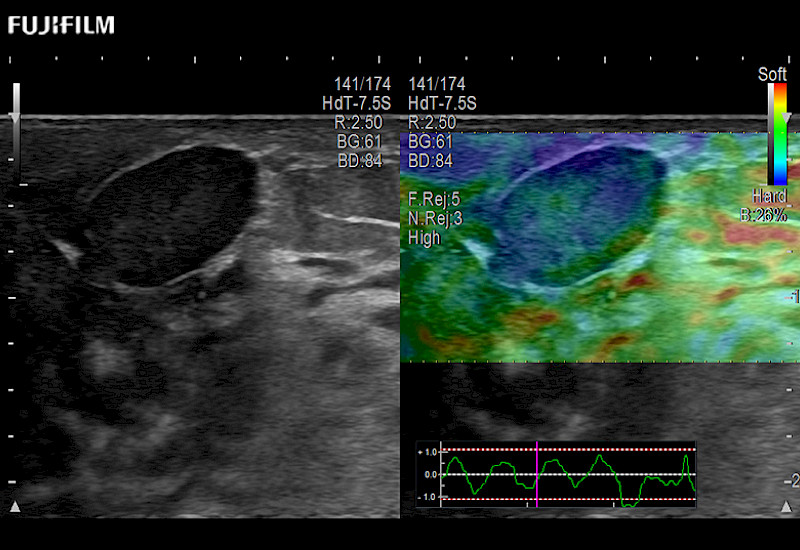

The ARIETTA 750 incorporates all of the proven technologies and functions that medical professionals have come to expect from Fujifilm Healthcare.

ARIETTA 750 is the definitive diagnostic ultrasound solution for any clinical setting - Private Office, Imaging Center, or Hospital. The ARIETTA platform provides the ultimate in clinical performance with its state-of-the-art features and large user-friendly display.

The ARIETTA 650 DI combines trusted Fujifilm Healthcare technologies and features tailored for surgical oncology.

Designed to meet the demands of surgeons, the ARIETTA 650 DI offers precise guidance. Its advanced capabilities and large, intuitive display offer accurate and efficient care in operating rooms and specialized surgical settings.